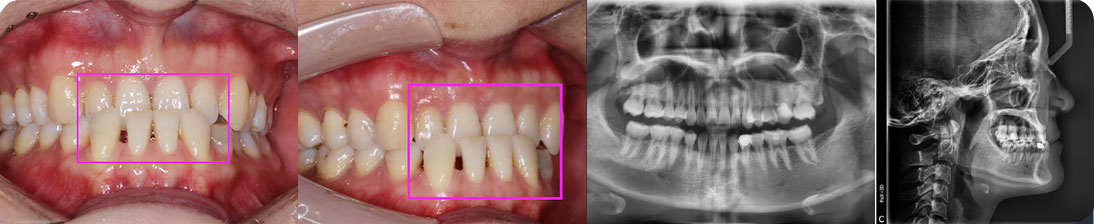

- 【診斷】

骨性Ⅱ類高角伴擁擠

上頜前突、下頜后縮、下前牙唇傾

下中線右偏2.5mm,21 35°扭轉(zhuǎn)13低位

打造醫(yī)生:德倫口腔正畸中心熊小琴主任

- 【治療方案】

拔除3顆多余的咬合不正的智齒,通過支抗釘控制

失狀向和垂直向,推上、下牙遠(yuǎn)移解決擁擠改善前

突,使整個(gè)頜平面逆時(shí)針旋轉(zhuǎn),改善了下頜后縮的

情況

矯治前后對(duì)比

牙列整平排齊,前牙內(nèi)收;覆蓋、覆合正常;尖牙和磨牙達(dá)到中性關(guān)系;上下中線對(duì)齊;下頜后縮改善